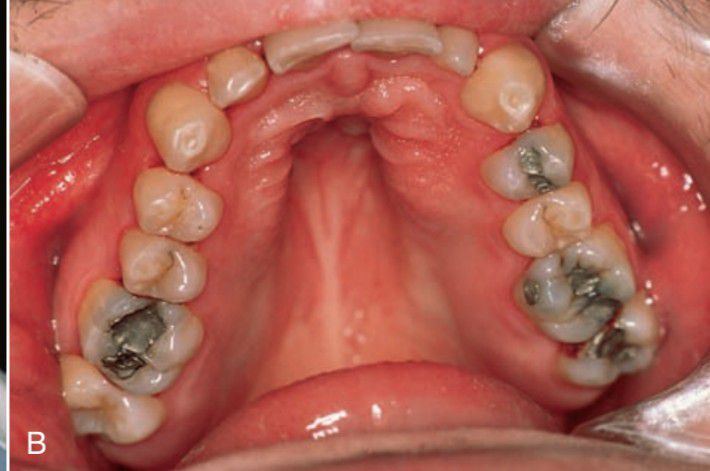

High arched palate with decreased width seen in down syndrome